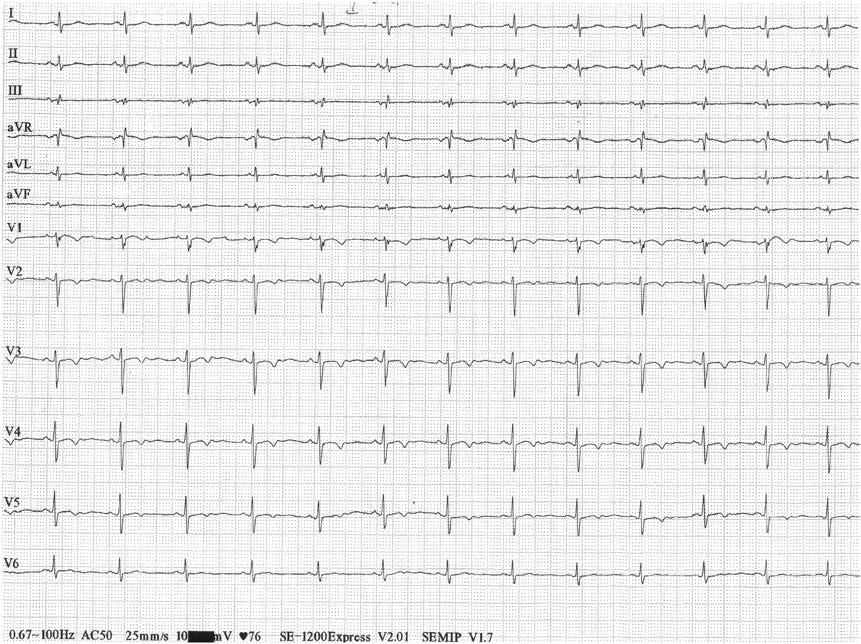

患者老年女性,主因"持续胸痛36小时"至当地医院就诊,既往有高血压、糖尿病史多年,有吸烟史,否认饮酒史。就诊后查体未见明显异常。于是做了一份心电图(图1)。注意就是这份心电图!

图1 就诊后第1份心电图,Ⅱ、Ⅲ、aVF导联ST段抬高,Ⅰ、aVL导联ST段压低

看到这份心电图,接诊医生顿时表情严肃、情绪紧张起来,考虑"急性下壁心肌梗死",于是他立即安排化验,结果除了血糖稍高外,肌钙蛋白I未见异常,随后他立即安排患者转至上一级医院就诊。

转诊后,上级医院的医生立即给患者复查心电图(图2)和肌钙蛋白I,并安排床旁超声心电图检查。结果发现心电图下壁导联回落至基线水平,除胸前导联T波轻度倒置外,余未见明显异常。超声心动图提示左室轻度肥厚,左室射血分数正常,左室壁未见节段性运动异常。此时实验室检查结果也出来了,肌钙蛋白I仍未升高。

图2 第2份心电图,Ⅱ、Ⅲ、aVF、Ⅰ、aVL导联ST段恢复至基线水平

患者病史、实验室检查、冠脉造影检查都是相对可靠的,那么心电图呢?仔细看这份心电图,还真有些不对劲的地方:①所有导联每个心动周期的ST段形态差异较大;②如果考虑下壁导联缺血,Ⅱ导联ST段却没有抬高。

此时我们考虑到,李鬼出现了--冒充下壁缺血。是什么原因呢?这其实是一种伪差,多见于电极接触不良。而该病例考虑左侧肢体导联接触不良所致。

因为大部分心电图机通常只记录Ⅰ、Ⅱ导联电位,其他肢体导联电位是通过Ⅰ、Ⅱ导联电位计算出来的,因此一旦干扰到这二者之一,均可影响到其他导联。该患者左侧电极接触不良,因此对应的Ⅰ、Ⅲ导联会受影响。

图3 肢体导联电极